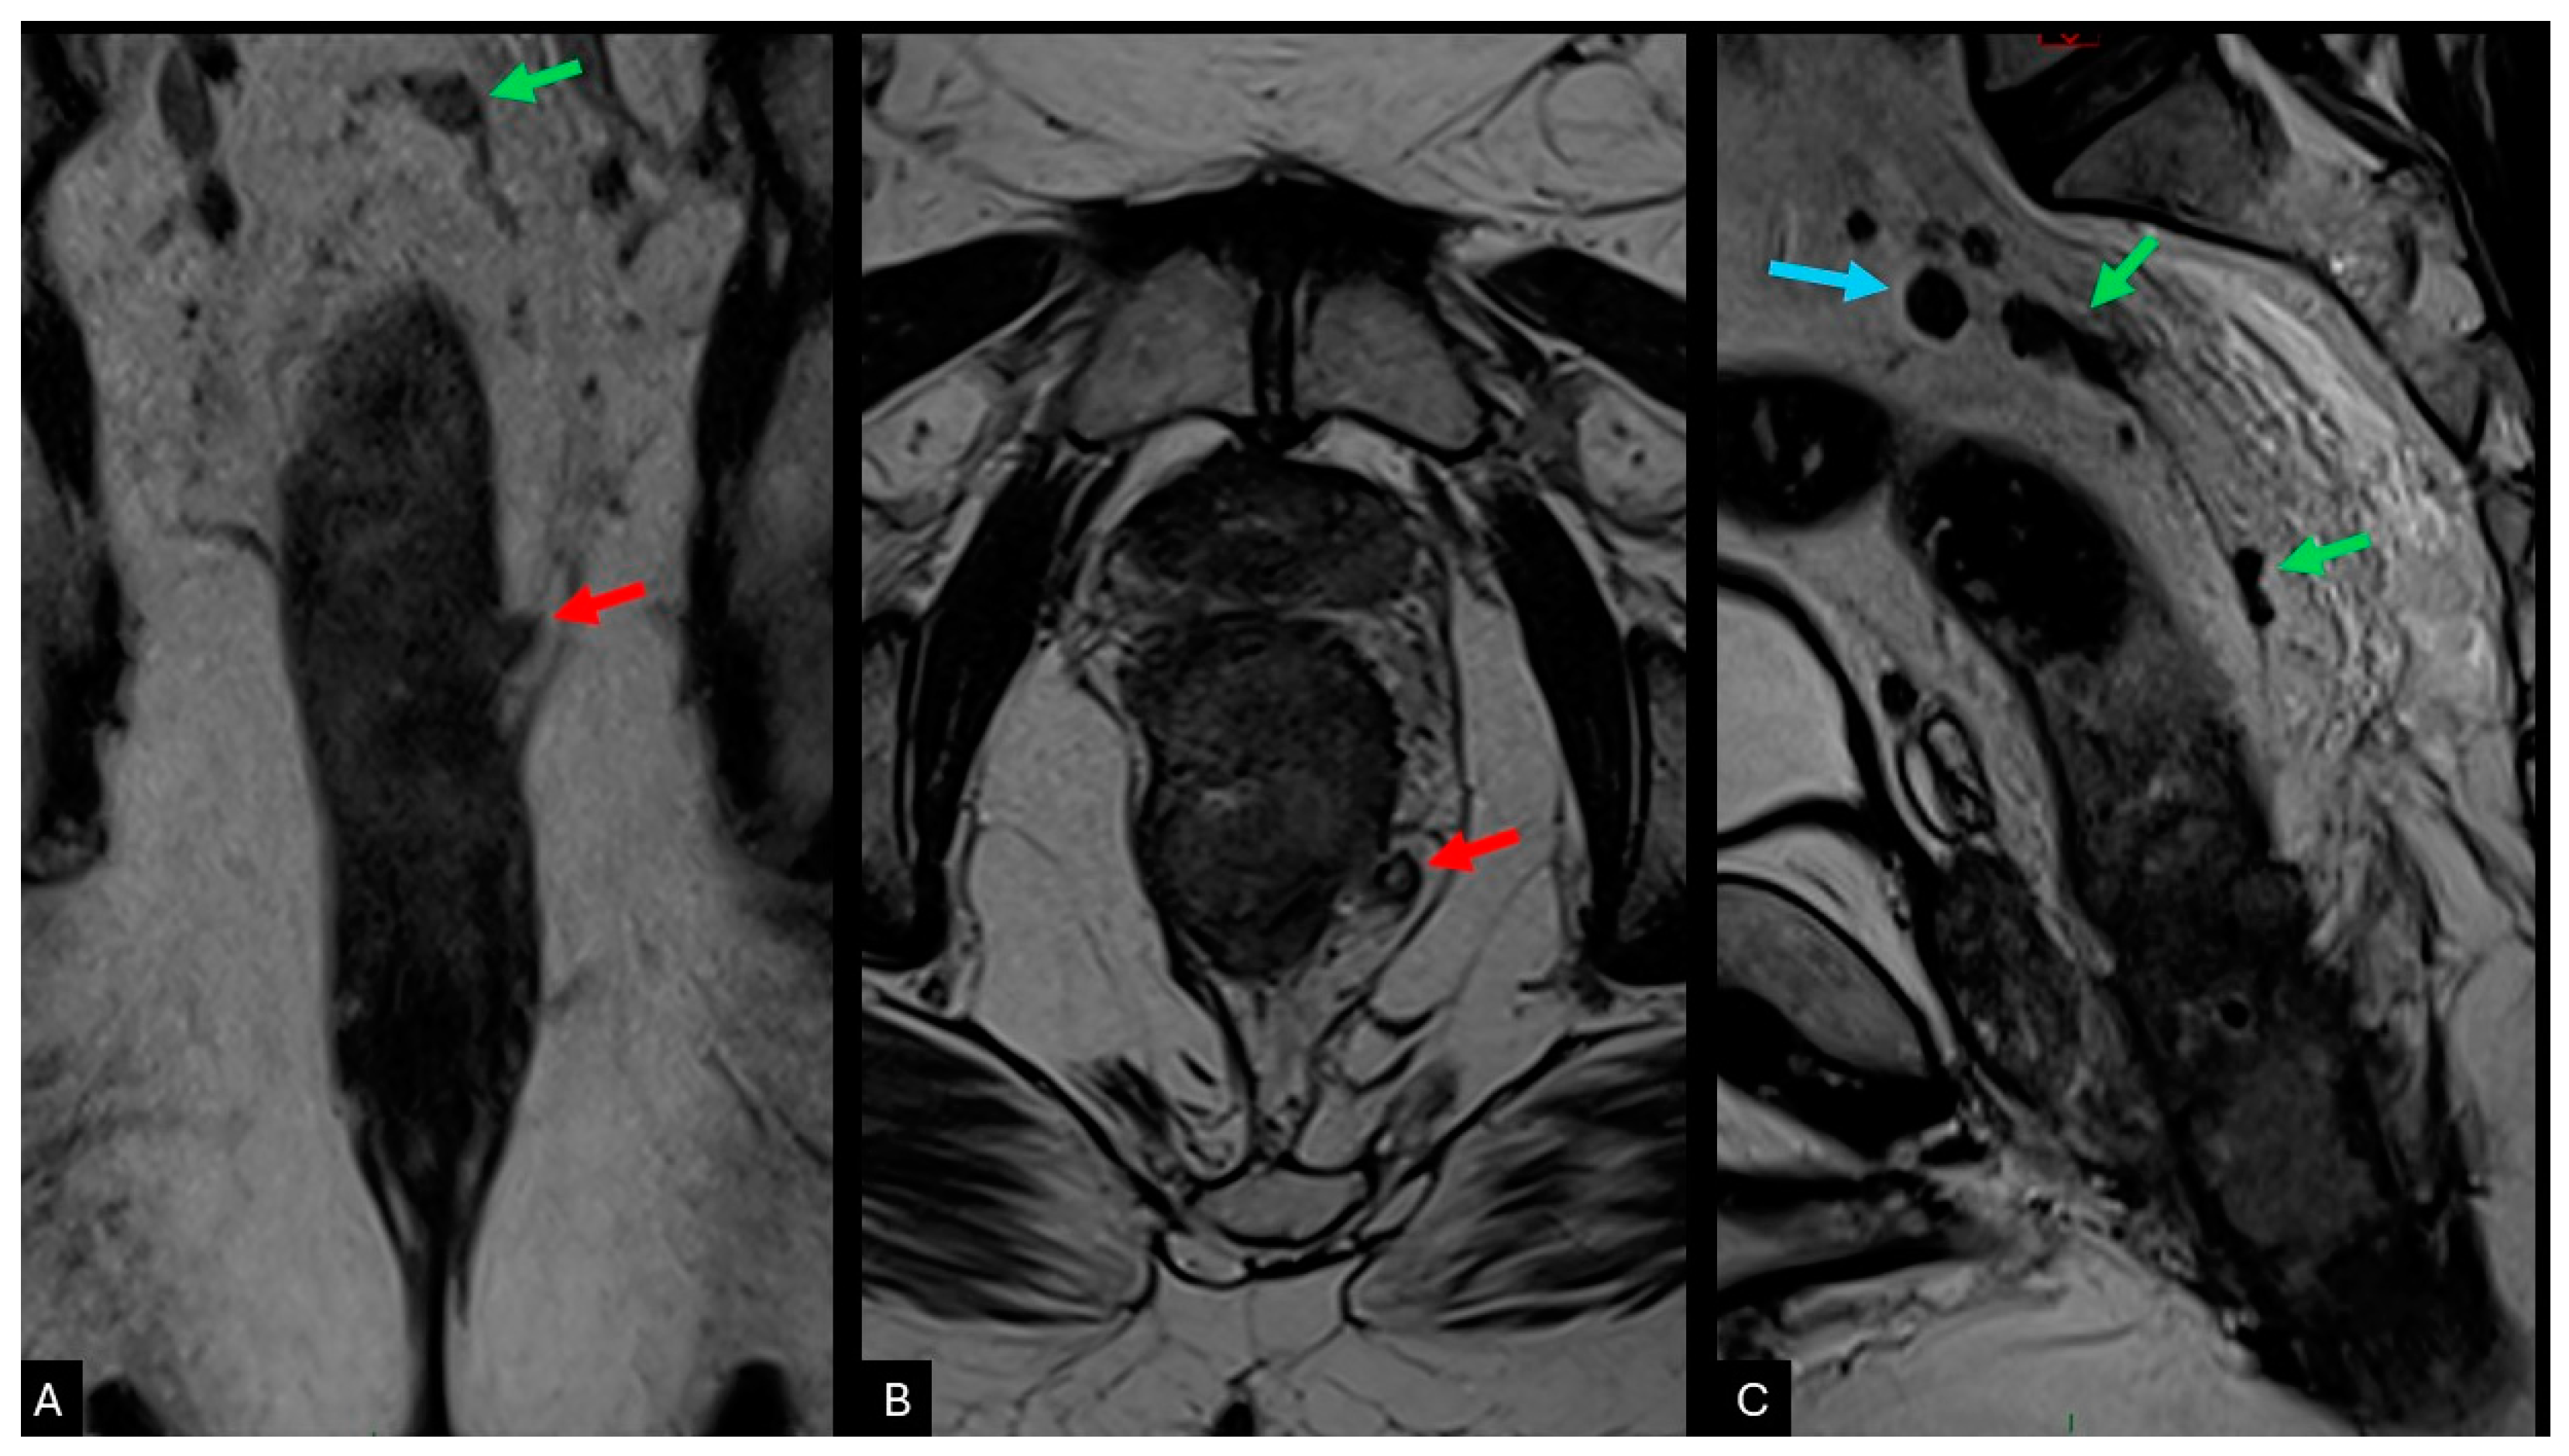

2.3. Extramural Venous Invasion (EMVI)

| EMVI | Intermediate signal within the mesorectal vessels, with a loss of normal hypointense flow void; additional features include irregular contours and increased calibre of the mesorectal vessels; should be documented both pre- and post-treatment; |